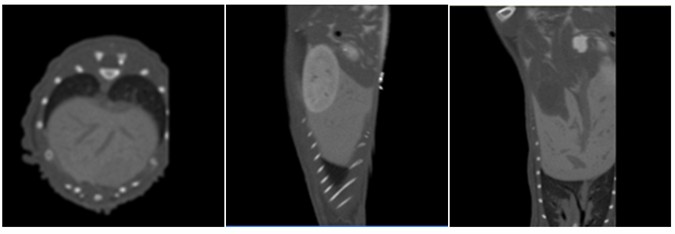

圖4編號為N的C57小鼠的橫截面、矢狀面、冠妝面視圖

(其中紅線內(nèi)所表示的區(qū)域為腫瘤組織)